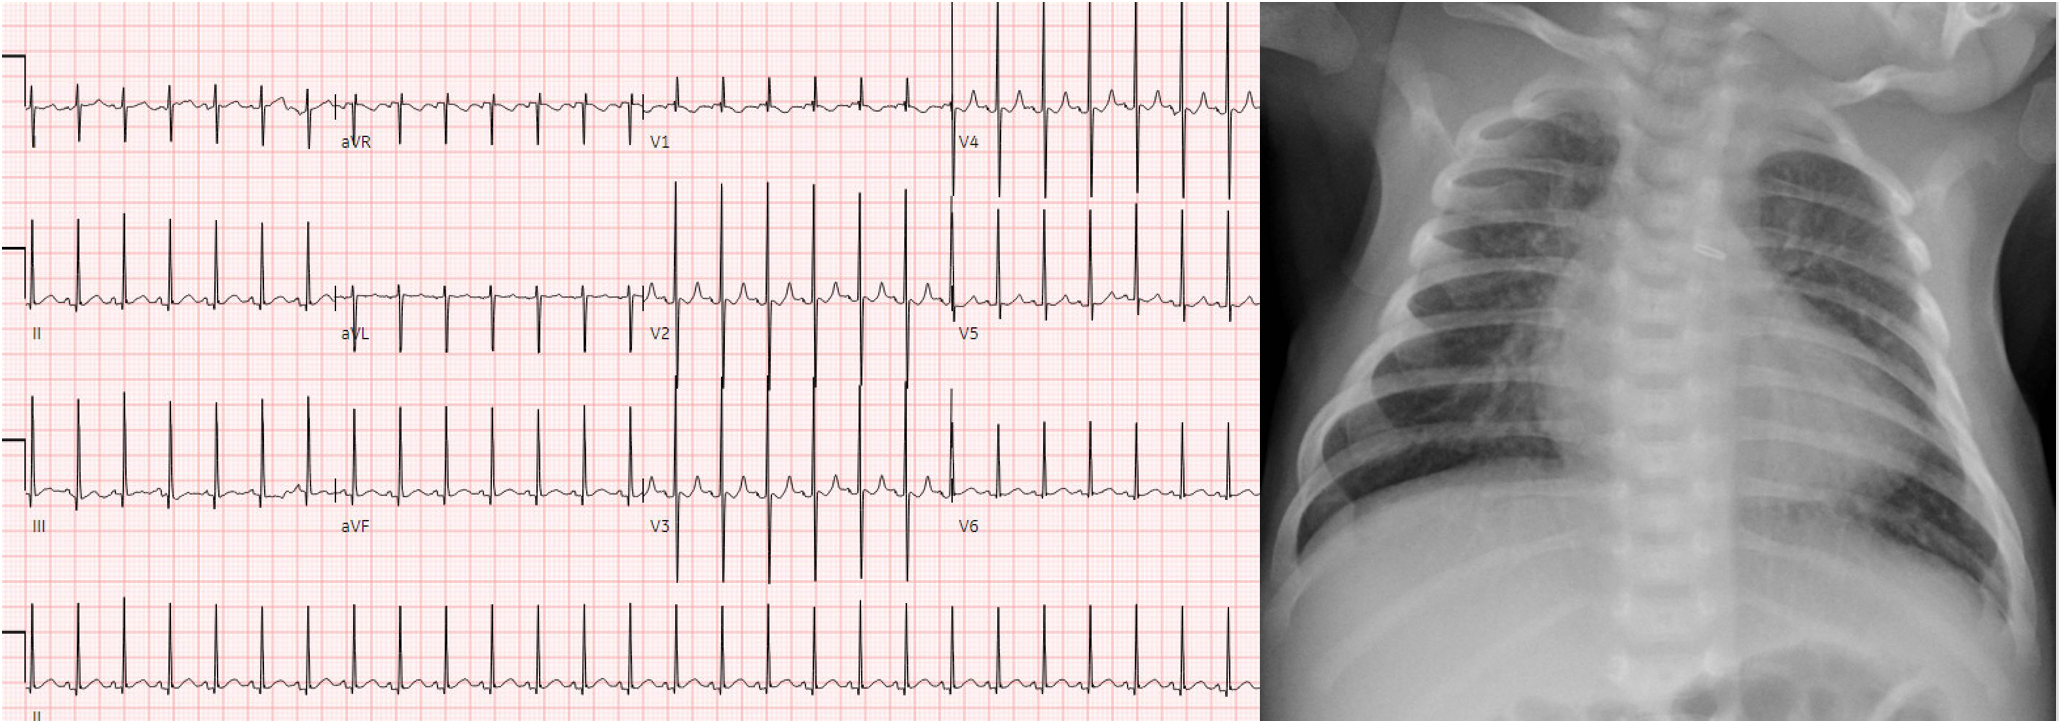

Patient 1 was born at 41 weeks gestation in January 2023 and had a post-natal diagnosis of d-TGA with intact ventricular septum. After birth, he had severe cyanosis and required urgent balloon atrial septostomy due to hypoxia and acidosis (pre-procedure pH 7.28, PaO2 37 mmHg, lactate 3.5 mmol/L). He underwent surgery on the day of life (DOL) 6 with an ASO including the LeCompte maneuver. He had no major complications and was transferred to the cardiac step-down unit (CSU) on DOL 10. He did well thereafter, tolerating full feedings by mouth and weaning to typical medications for home including a daily dose of furosemide. Post-operative echocardiograms showed no concerning findings after the ASO, specifically no significant branch pulmonary artery stenosis, residual atrial level shunting, neoaortic valve insufficiency, or evidence of elevated right ventricular systolic pressure. He continued to require nasal cannula (NC) oxygen to prevent hypoxia, however. Oxygen saturations off supplemental oxygen were 80%–85%. Chest radiography was reassuring and clinically there were no signs of respiratory insufficiency. Fig. 1 shows the post-operative electrocardiogram and chest radiography.

Figure 1: Post-operative electrocardiogram and chest radiograph of patient 1. Findings include normal sinus rhythm with normal intervals and repolarization, as well as no radiographic signs of pleural effusion or significant intrapulmonary process to explain hypoxia